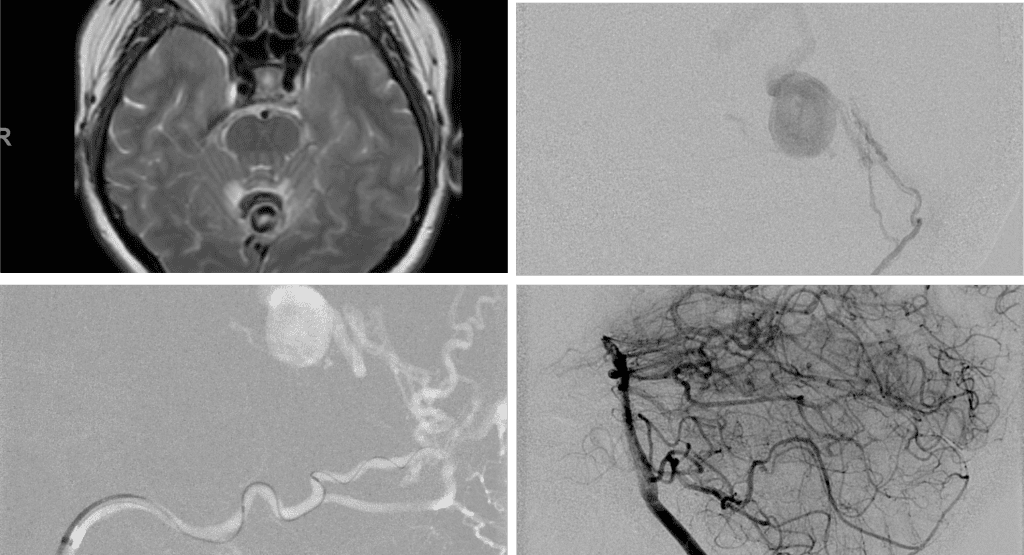

No severe neurologic deficits were observed initially. Her cerebral angiogram revealed a high flow Dural arterial venous fistulous malformation of the tentorium supplied by the bilateral external carotid and left vertebral arteries into a large venous varix within the fourth ventricle at the site of the hemorrhage. Deep venous drainage is observed into the Galenic and Straight Sinus of the posterior fossa (Figure 2).

Figure 2. [A] Ruptured Varix/Aneurysm of the Deep Venous Posterior Fossa drainage and AV shunting (arrows) [B] Posterior Meningeal Artery Fistula [C] Right Middle Meningeal Artery Fistula [D] Post embolization Left Vertebral Angiogram demonstrates resolution of the high flow and pressure A-V Shunting following successful embolization with liquid embolic (NBCA).